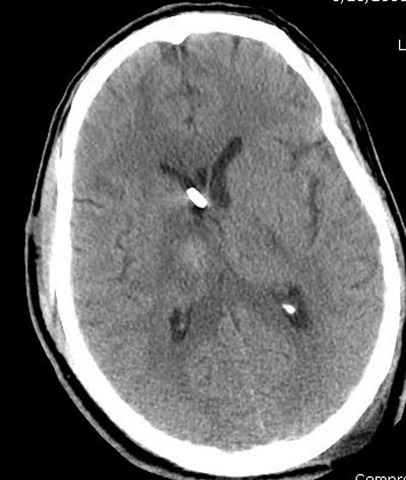

Наблюдается службой травмы и нейрохирургии (ICP) Increased Intracranial Pressure by ventricular cateter

монииторинг